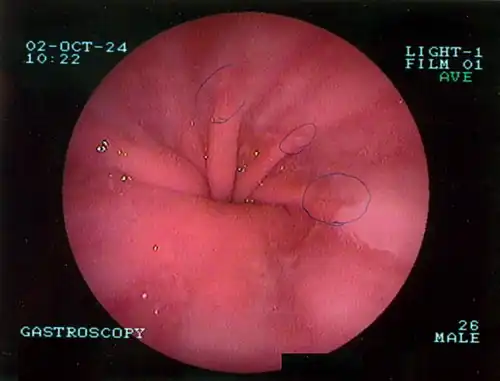

The diagnosis of a hiatal hernia is typically made through an upper GI series, endoscopy, high resolution manometry, esophageal pH monitoring, and computed tomography (CT). Barium swallow, as in the upper GI series, allows the size, location, stricture, and stenosis of oesophagus to be seen. It can also evaluate the oesophageal movements. Endoscopy can analyse the esophageal internal surface for erosions, ulcers, and tumours.

Meanwhile, manometry can determine the integrity of esophageal movements and the presence of esophageal achalasia. pH testing allows the quantitative analysis of acid reflux episodes. A CT scan is useful in diagnosing complications of hiatal hernia, such as gastric volvulus, perforation, pneumoperitoneum, and pneumomediastinum.[8]